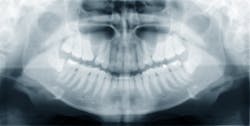

ONJ is also linked to drugs like denosumab (Prolia), an injection drug used to treat osteoporosis, but no causal relationship has been established. (5) Bisphosphonates and denosumab reduce the rate of bone turnover and possibly decrease the effectiveness of the body’s resistance to infection. (6) Researchers of one study conclude that infection should be viewed more critically in ONJ, and that “ONJ with infection at the epicenter could justify temporary discontinuation of the ‘offending drug’ to allow recovery of macrophage production and function.” (6) Traumatic procedures should be minimized or eliminated, and harmful pathogens should be prevented from reaching the bone surface by optimal hygiene procedures. (6)

Another review illuminated the role and mechanisms of diabetes in medication-caused ONJ. Factors may include damage to the microvasculature, “endothelial cell dysfunction, reduced remodeling of bone, and increased apoptosis of osteoblasts and osteocytes.” (7) They also suspect that an impaired immune system can promote inflammation, and be an additional factor in ONJ.